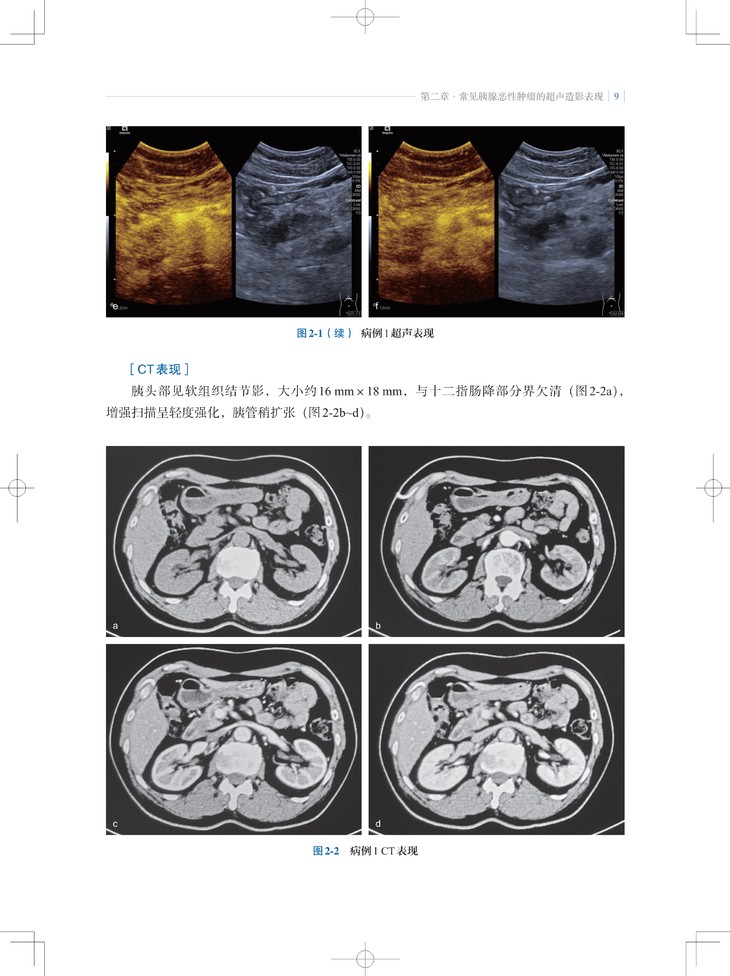

本书是“东方超声文库”系列之一,介绍了超声造影剂和实时超声造影技术在胰腺肿瘤诊疗领域的最新应用。内容包括胰腺肿瘤的超声造影表现特点、诊断要点,超声造影在随访胰腺癌非手术治疗、预测胰腺切除术后并发胰瘘、胰腺癌微创介入治疗中的应用;此外,通过与胰腺肿瘤的CT、MRI等影像学表现的对比,让读者对超声造影检查技术有更全面的认识。

2. 内容实用:超声造影不但提高了胰腺肿瘤定性诊断的准确性,而且能反映胰腺肿瘤微血管的血流动力学改变,本书对从事胰腺肿瘤诊断和治疗的各领域、各级临床医师有实用指导意义。

3. 编写方式契合临床:不仅有胰腺肿瘤造影影像图,还有与CT/MRI等影像学表现的对比及手术照片。